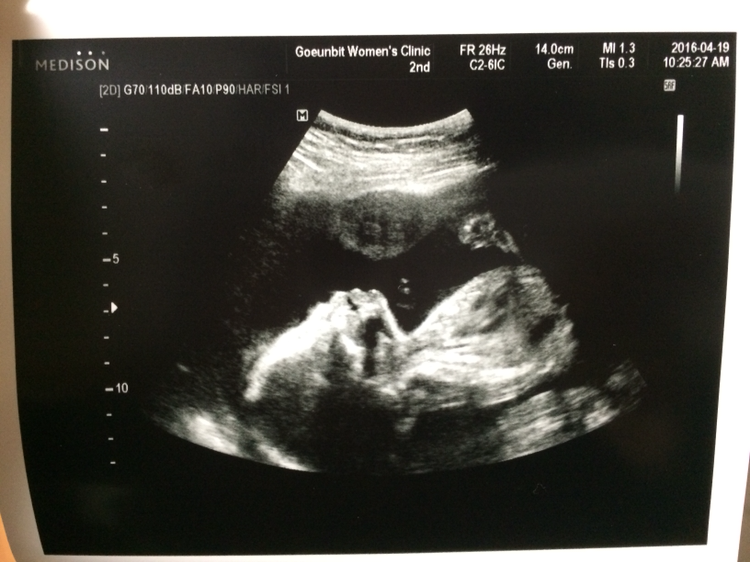

내 배에 올려진 초음파 기계. 그 기계가 움직이는 방향에 따라 아이의 작은 얼굴과 작은 손가락, 발가락, 심장 하나까지도 자세히 볼 수 있었다. 내 배속에 저렇게 작은 아이가 자라고 있다니.... 신기함과 신비로움이 공존하는 미묘한 감정이 내 안에 흐르고 있었다.

매번 검사하러 갈 때마다 많이 커 있는 아이. 선생님께서는 아기가 태동도 잘하고 있다고 칭찬을 해주셨다. 다만 19주부터 먹기 시작한 커피 때문인지 아니면 물을 너무 적게 먹어서인지 선생님께서는 양수가 조금 적다고 아이를 위해 물을 많이 먹어줘라고 하셨다. (당분간 커피는 끊는 걸로) 그리고 아이는 또 한 번 반전 없이 아들임을 입증했다. 또 다리를 벌리고 ‘엄마 난 아들이에요’를 아낌없이 보여주었다. 이제 조금씩 사람의 형태를 갖추어져 가고 있는 아이. 아이가 클수록 엄마가 된다는 설렘도 커져가는 것 같다. 19주 뒤엔 진짜 어떤 모습으로 태어날지 그 모습이 정말 궁금해진다.